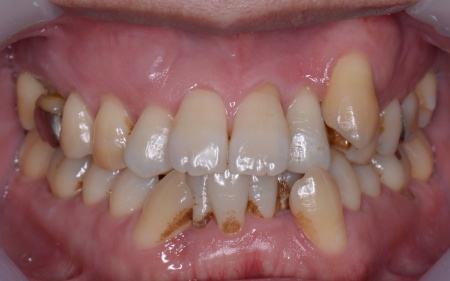

| カウンセリング | 拝見したところ、上下の歯は、ずれたりねじれたりしてデコボコに生えており、著しく歯並びが乱れていました。

またレントゲン撮影をして確認すると、右上前歯は顎の骨の中に埋まっている骨性埋伏(こっせいまいふく)の状態でした。 さらに、左下奥歯は重度の歯周病であり、歯を支えている骨が一部溶けていることが判明しました。 以上のことから、歯並びを整える矯正治療と歯周病の治療を併せて行う必要があると診断しました。 |